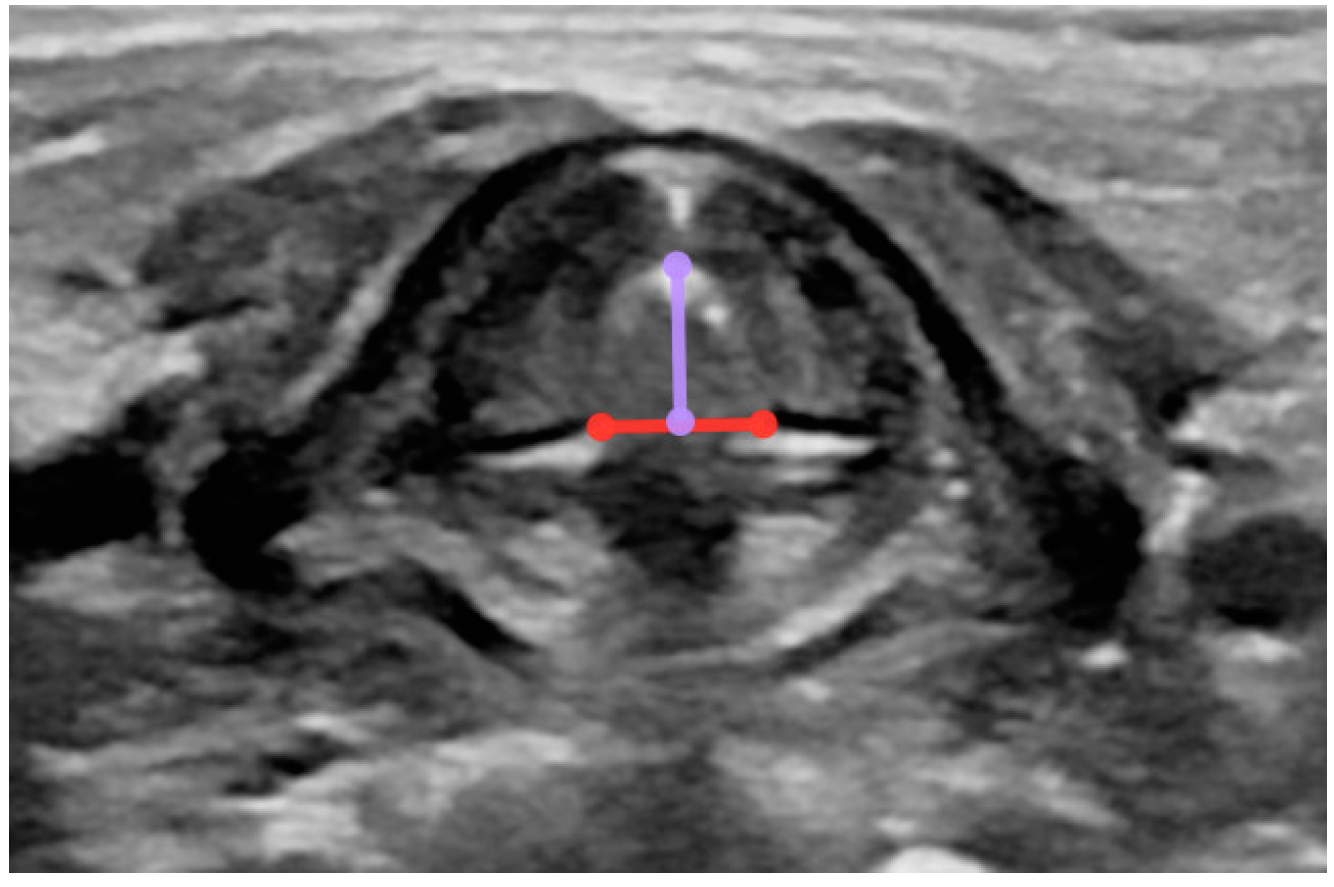

- Width of the larynx at the level of the glottis (measurement taken in the transverse plane from the external margins of the thyroid cartilage) (Figure A2);

- Depth of the larynx at the level of the glottis (measurement taken in the transverse view from the external margin of the thyroid cartilage to the external border of the annular cartilage) (Figure A2);